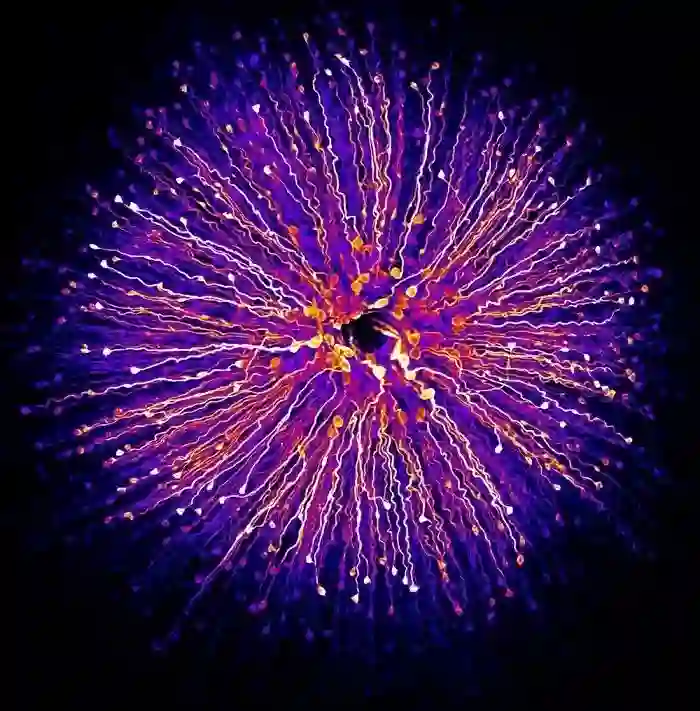

成纤维细胞

第11名:经历细胞分裂的人成纤维细胞,肌动蛋白(灰色),肌球蛋白II(绿色),DNA (洋红色)(Nilay Taneja和Dylan Burnette / 摄)。Nilay Taneja和Dylan Burnette 来自范德堡大学